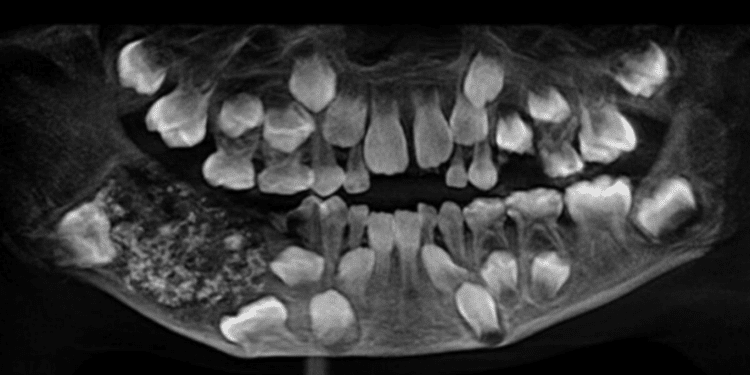

Um caso que entrou para os livros de odontologia chamou atenção na Índia: um menino de 7 anos, de Chennai, passou por uma cirurgia que revelou 526 dentes em miniatura dentro de uma massa na mandíbula.

A cirurgia, realizada em 2019 no Saveetha Dental College and Hospital, durou várias horas e permitiu a remoção de uma massa de cerca de 200 gramas. Dentro dela, os cirurgiões encontraram centenas de estruturas semelhantes a dentes, variando de 1 a 15 milímetros, cada uma com coroa e raiz completas.

(Saveetha Dental College and Hospitals/Divulgação) 526 estruturas foram encontradas no menino

“Foram necessárias cinco horas de busca meticulosa para remover todos os dentes minúsculos do espécime, que lembrava pérolas em uma ostra”, informou o hospital na época. A equipe descreveu o achado como uma verdadeira caixa de Pandora de dentes em miniatura.

Caso histórico